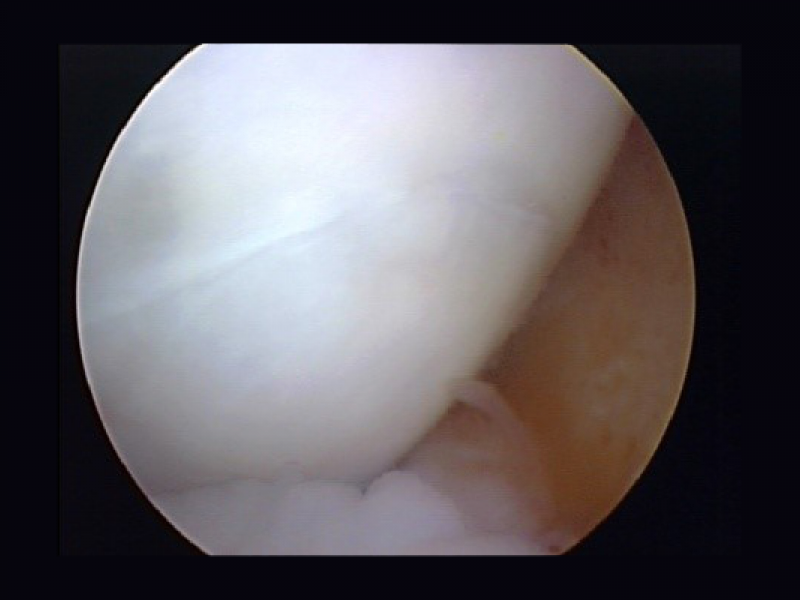

Dr. Farrah Monibi (pictured) presented her work in the area of meniscal tissue engineering and Dr. Jimi Cook presented the initial outcomes of patients undergoing